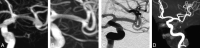

Fig 3.

A, Preoperative DSA shows a wide-neck basilar artery aneurysm. B, The WEB device is deployed in the aneurysm. C and D, Six-month DSA (oblique and lateral views) shows a small aneurysm remnant. E and F, Twenty-one-month DSA (oblique and lateral views) shows that the aneurysm remnant has not grown.